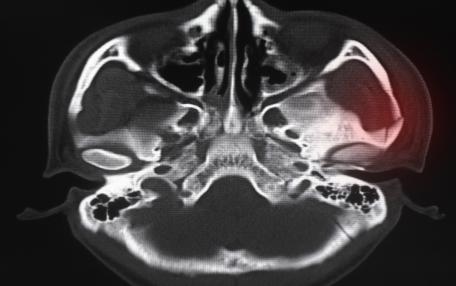

Il condilo si trova in diverse parti del corpo, una di queste è l'area mandibolare e per questo si parla di mandibola condilo. Il condilo mandibolare si trova specificamente sul lato superiore della mascella inferiore e si articola anche con l'osso temporale per formare l'ATM (articolazione temporomandibolare). Il condilo mandibolare ha una parte ruvida in cui arriva il legamento laterale esterno e una presa che si collega con il muscolo pterigoideo laterale.

L'articolazione temporomandibolare (chiamata anche complesso articolare craniomandibolare) è l'articolazione sinoviale simile a bicondilo che esiste tra l'osso temporale e la mandibola. In realtà sono due articolazioni, una su ciascun lato della testa, che funzionano in sincronia. È una delle poche articolazioni mobili della testa, insieme alla testa dell'atlantooccipitale. L'articolazione tempo-mandibolare è costituita da un insieme di strutture anatomiche che, con l'aiuto di Anatomia dell'ATM e di specifici gruppi muscolari, permette alla mandibola di eseguire vari movimenti applicati alla funzione masticatoria (apertura e chiusura, protrusione, retrusione, lateralità). Il Dizionario dei termini medici lo descrive come un'articolazione bicondilare tra la fossa mandibolare e il tubercolo articolare dell'osso temporale sopra e il condilo della mandibola. L'ATM è formata dal condilo della mandibola con le fosse mandibolari della porzione petrosa dell'osso temporale. Tra questi c'è un cuscinetto fibroso: il disco articolare. Sopra e sotto questo disco ci sono piccoli compartimenti a forma di sacco chiamati cavità sinoviali. L'intera ATM è circondata da una capsula articolare fibrosa. L'aspetto laterale di questa capsula è più spesso ed è chiamato legamento temporomandibolare. Ha la funzione di impedire al condilo di spostarsi troppo in basso e indietro oltre a fornire resistenza al movimento laterale. I condili temporale e mandibolare sono gli unici elementi attivi che partecipano alla dinamica articolare, motivo per cui questa articolazione è considerata una doppia diartrosi condilare. L'artrosi dell'articolazione temporomandibolare è una malattia degenerativa unilaterale dell'articolazione della mandibola.

Il condilo si trova in diverse parti del corpo, una di queste è l'area mandibolare e per questo si parla di mandibola condilo. Il condilo mandibolare si trova specificamente sul lato superiore della mascella inferiore e si articola anche con l'osso temporale per formare l'ATM (articolazione temporomandibolare). Il condilo mandibolare ha una parte ruvida in cui arriva il legamento laterale esterno e una presa che si collega con il muscolo pterigoideo laterale.

L'articolazione temporomandibolare (chiamata anche complesso articolare craniomandibolare) è l'articolazione sinoviale simile a bicondilo che esiste tra l'osso temporale e la mandibola. In realtà sono due articolazioni, una su ciascun lato della testa, che funzionano in sincronia. È una delle poche articolazioni mobili della testa, insieme alla testa dell'atlantooccipitale. L'articolazione tempo-mandibolare è costituita da un insieme di strutture anatomiche che, con l'aiuto di Anatomia dell'ATM e di specifici gruppi muscolari, permette alla mandibola di eseguire vari movimenti applicati alla funzione masticatoria (apertura e chiusura, protrusione, retrusione, lateralità). Il Dizionario dei termini medici lo descrive come un'articolazione bicondilare tra la fossa mandibolare e il tubercolo articolare dell'osso temporale sopra e il condilo della mandibola. L'ATM è formata dal condilo della mandibola con le fosse mandibolari della porzione petrosa dell'osso temporale. Tra questi c'è un cuscinetto fibroso: il disco articolare. Sopra e sotto questo disco ci sono piccoli compartimenti a forma di sacco chiamati cavità sinoviali. L'intera ATM è circondata da una capsula articolare fibrosa. L'aspetto laterale di questa capsula è più spesso ed è chiamato legamento temporomandibolare. Ha la funzione di impedire al condilo di spostarsi troppo in basso e indietro oltre a fornire resistenza al movimento laterale. I condili temporale e mandibolare sono gli unici elementi attivi che partecipano alla dinamica articolare, motivo per cui questa articolazione è considerata una doppia diartrosi condilare. L'artrosi dell'articolazione temporomandibolare è una malattia degenerativa unilaterale dell'articolazione della mandibola.